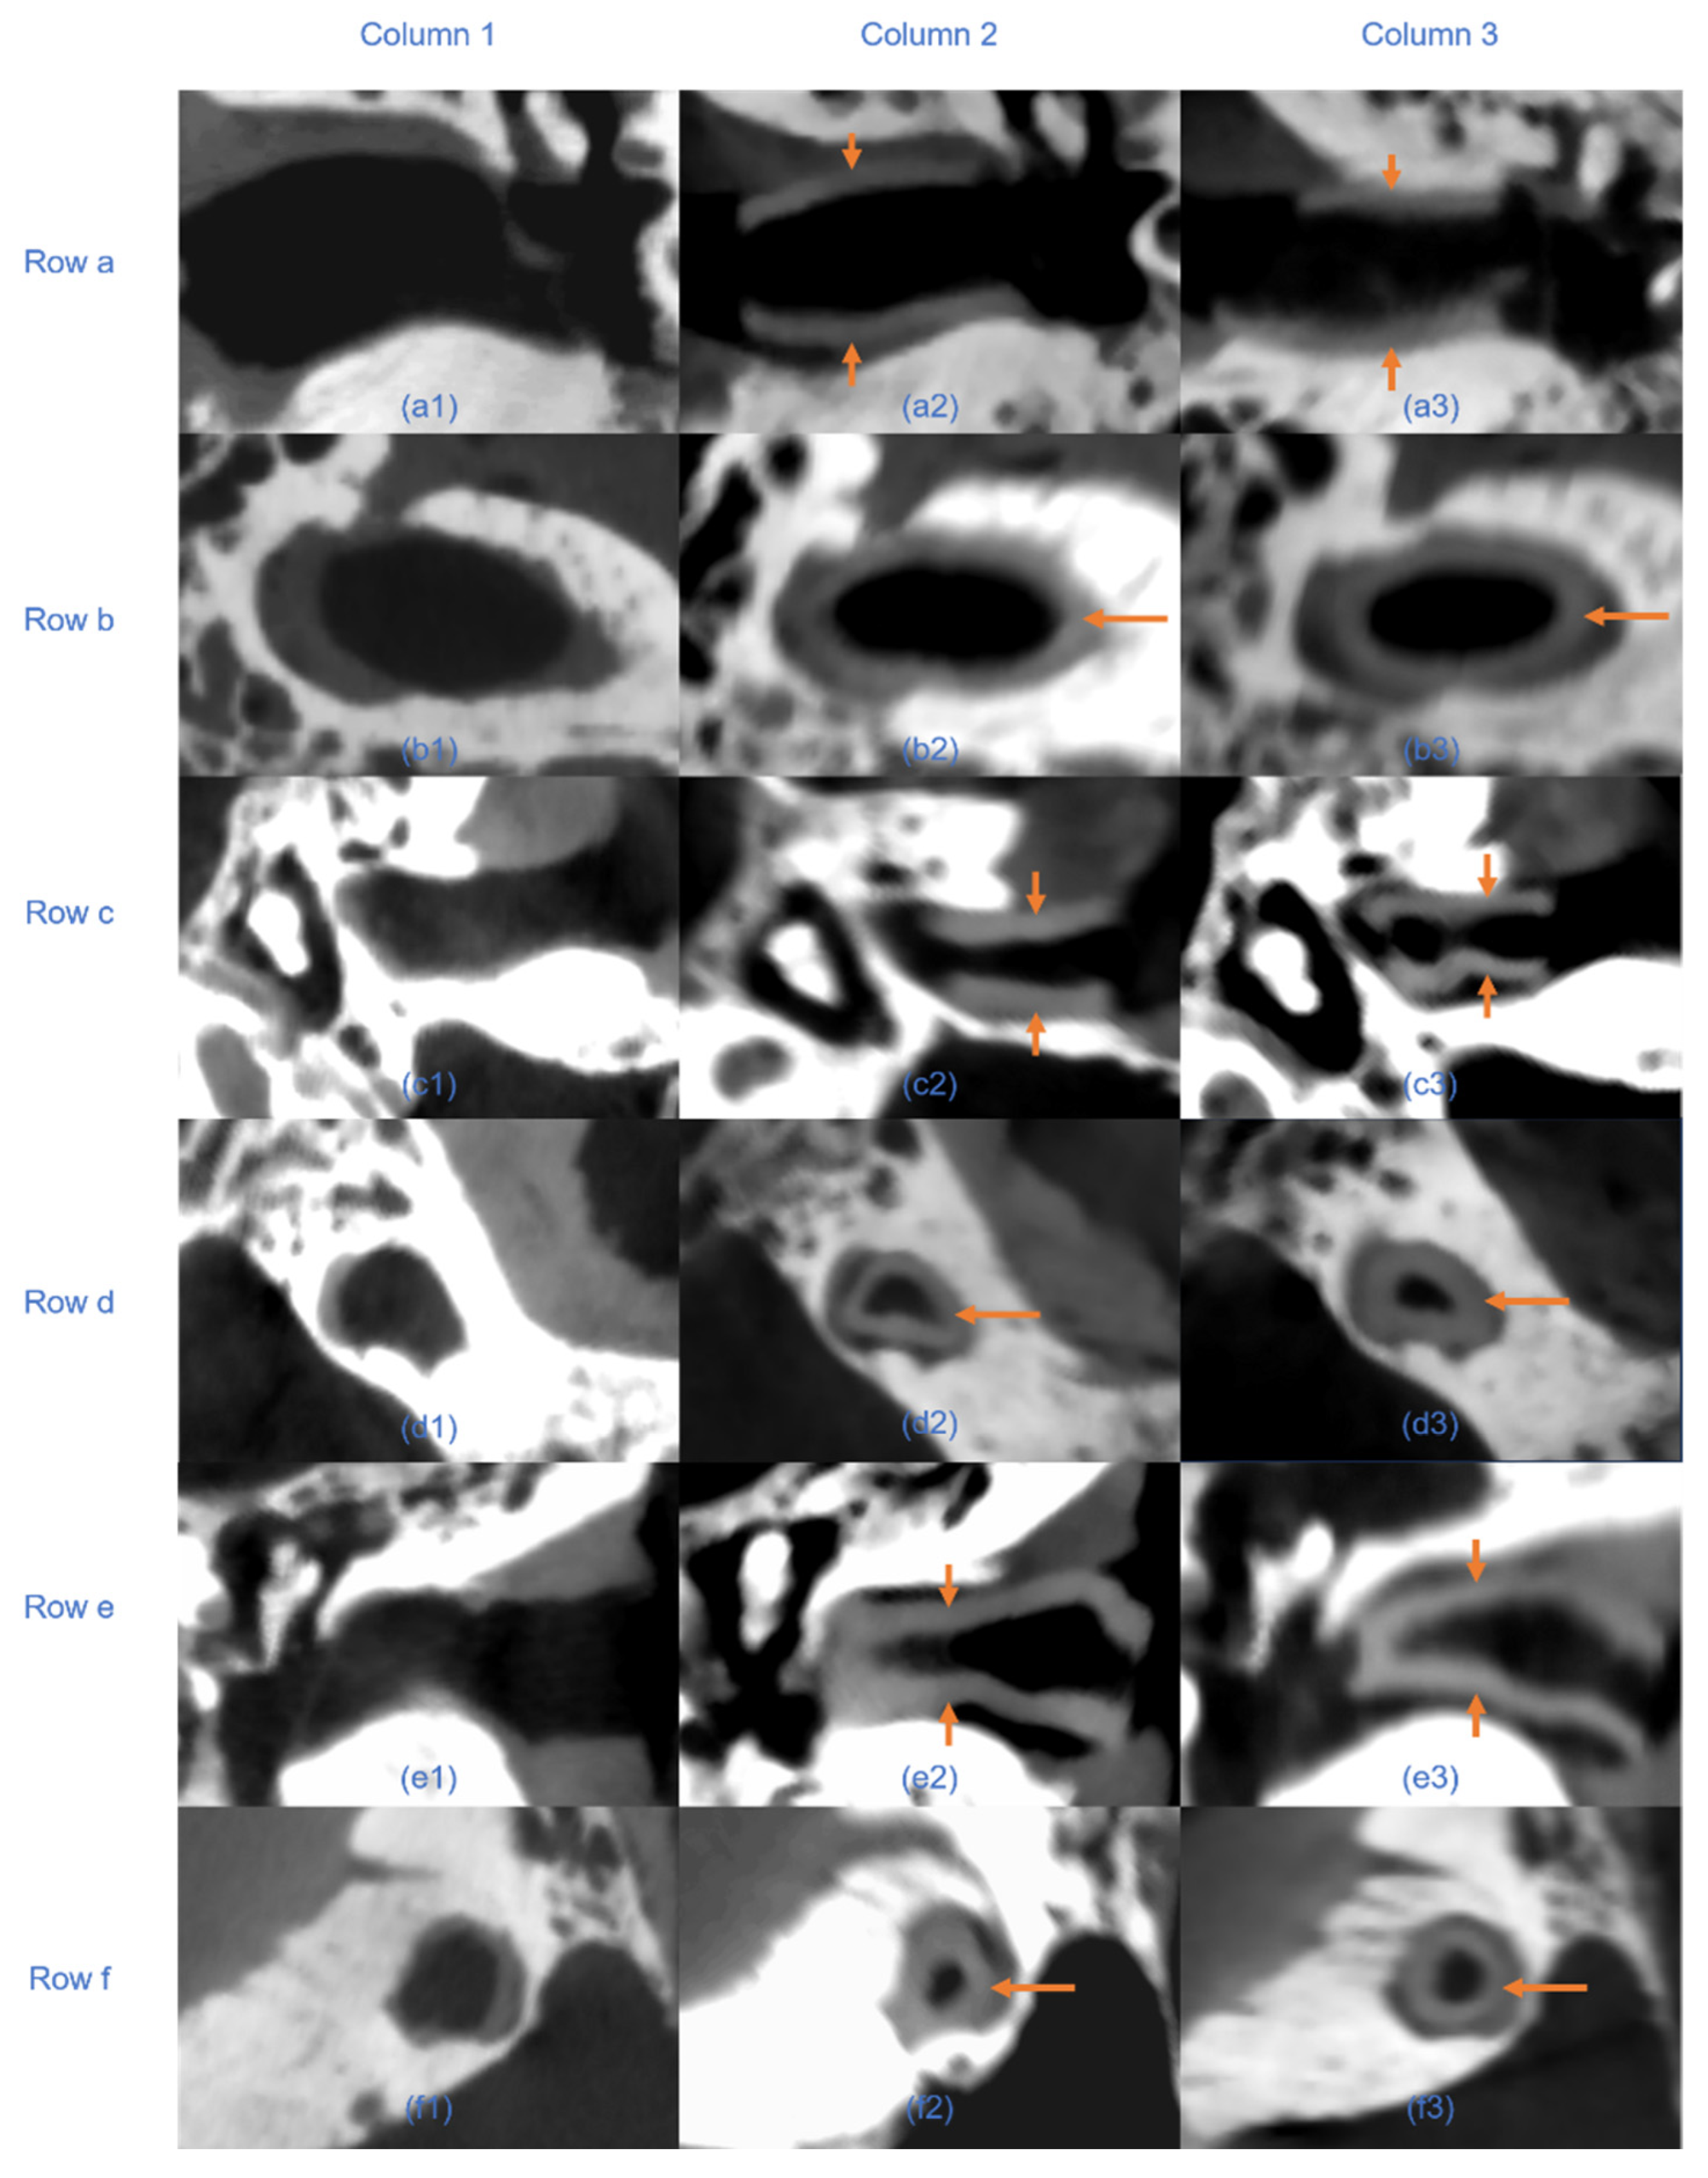

Figure 10. Axial and sagittal CBCT views of three human cadaver temporal bone specimens before and after implantation of EECIs derived from manual and automated segmentation. Columns: Column 1 shows pre-implantation scans; column 2 shows post-implantation with implants based on manual segmentation; column 3 shows post-implantation with plugin-based implants. Rows: a/c/e show axial views, and b/d/f show sagittal views of specimens 1, 2, and 3, respectively. Arrows indicate the position of the implanted EECIs. In axial views, bilateral arrows denote implant boundaries; in sagittal views, single arrows indicate overall implant alignment.

Quantitative analysis of the RMS surface distances revealed that the EECI models generated by manual segmentation exhibited RMS distances of 0.05 mm, 0.08 mm, and 0.06 mm relative to the EEC surface, while those generated by automated segmentation had RMS distances of 0.05 mm, 0.11 mm, and 0.12 mm. The results indicated a high degree of consistency and segmentation precision across both approaches (Figure 7). The otorhinolaryngologist rated all 3D-printed EECIs, regardless of segmentation method, as easily insertable and properly positioned. The performance evaluations for the insertion process are summarized in Table 3. Data are presented as mean values ± standard deviations. Specifically, all implants fit tightly against the bony walls of the EEC, with no visible gaps or misalignments along the edges (Figure 8). Post-insertion CBCT imaging further validated the fitting accuracy, demonstrating complete coverage of the EEC with no observable displacement or deformation of the implants (Figure 9 and Figure 10). In addition, the EECI models obtained by manual and automated segmentation before implantation demonstrated high spatial alignment and geometric consistency with the EEC model (Figure 11). Similarly, the comparison of EECI models before and after implantation, generated using both manual and automated segmentation methods, showed high geometric stability with minimal deformation, highlighting the accuracy and conformity of the implants. These findings indicate that the 3D printing and preparation process maintained high geometric accuracy, and no obvious deformation was observed after implantation. The RMS distances between the EEC model and the manually segmented EECI model after implantation were 0.22 mm, 0.18 mm, and 0.27 mm, while the RMS distances between the EEC model and the automatically segmented EECI model were 0.15 mm, 0.16 mm, and 0.22 mm, respectively (Figure 7). This further confirmed that the implant had high geometric stability and a close fit with the EEC.